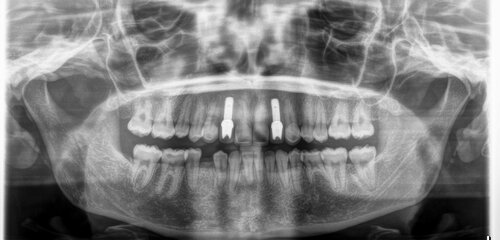

Before

This patient was congenitally missing these front teeth, which never developed.

Pre-treatment panoramic dental image

During

We placed two narrow dental implants into the bone to replace the missing tooth roots.